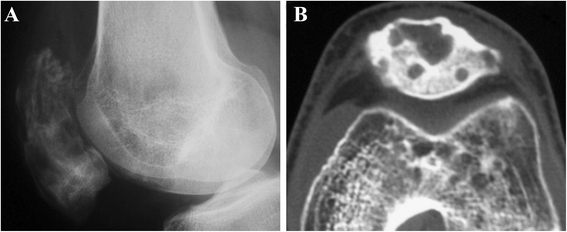

The patella is an uncommon location for cancerous occurrence and development. The majority of tumors of the patella are benign, with a significant incidence of giant cell tumors and chondroblastoma. With the development of modern diagnostic technologies, there appear however many other histological types which raise challenges of diagnosis and treatment. In this article, we review the reported histological types of primary patellar tumors. Specifically, epidemiology, symptomatology, imageology, histopathology, and treatment options for these histological lesions will be discussed, respectively. As there is an increasing focus on the diagnosis and the treatment of these lesions, the availability of the integrated information about primary patellar tumors becomes more significant.